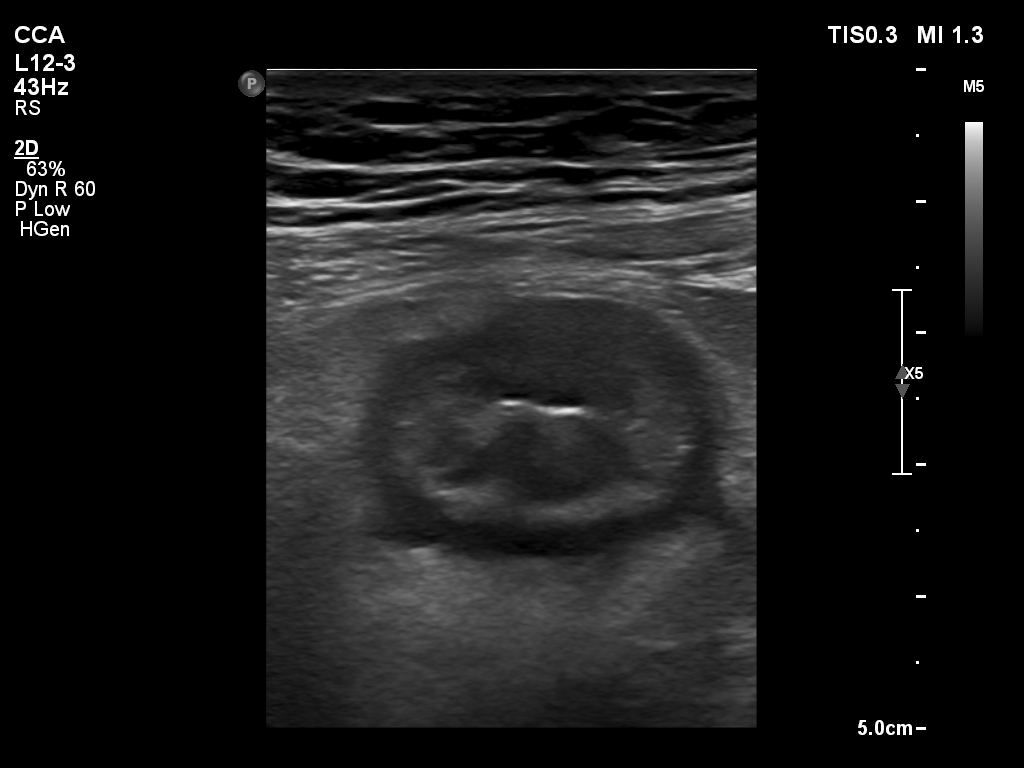

结肠超声

结肠超声是应用高频线振探头扫查炎性肠病患者的病变肠管,对病变范围、增厚程度、狭窄情况、炎症阶段进行评估与诊断。

虽然肠道超声检查因为设备检查原理的限制,具有可视区域范围小、缺少全景视角的不足,但超声检查也同时具有费用低、设备易获得、无辐射、可实时评估肠蠕动、空间分辨率高、不需要镇静、麻醉或抗蠕动药物、不需要口服或静脉注射造影剂等优势。

超声检查能实时观察肠壁的增厚、充血、管腔异常和蠕动改变;肠周系膜组织的炎性改变、纤维脂肪增生、局部淋巴结增大、瘘管和瘘道的形成及异常积液及肛周病变。为临床诊断和治疗方案的制定提供支持,同时适用于炎性肠病患者的检查及治疗后的复查。